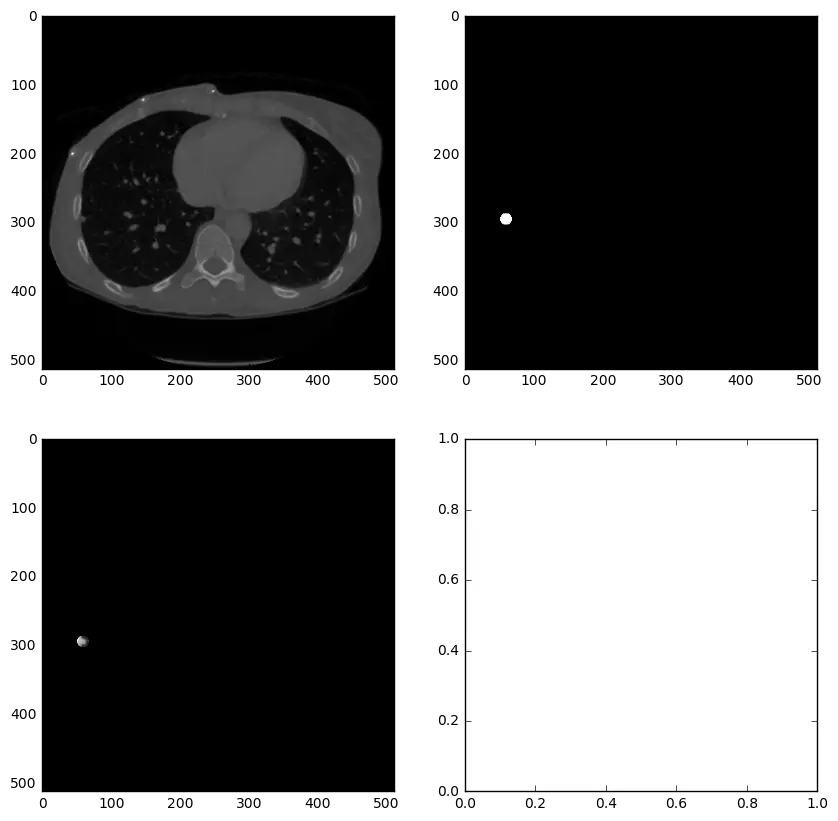

3.5 查看结节

以下代码用于查看原始CT和结节mask。其实就是用matplotlib打印上一步存储的npy文件。

import matplotlib.pyplot as plt

imgs = np.load(output_path+'images_0.npy')

masks = np.load(output_path+'masks_0.npy')

for i in range(len(imgs)):

print "image %d" % i

fig,ax = plt.subplots(2,2,figsize=[8,8])

ax[0,0].imshow(imgs[i],cmap='gray')

ax[0,1].imshow(masks[i],cmap='gray')

ax[1,0].imshow(imgs[i]*masks[i],cmap='gray')

plt.show()

raw_input("hit enter to cont : ")

示例结节和mask